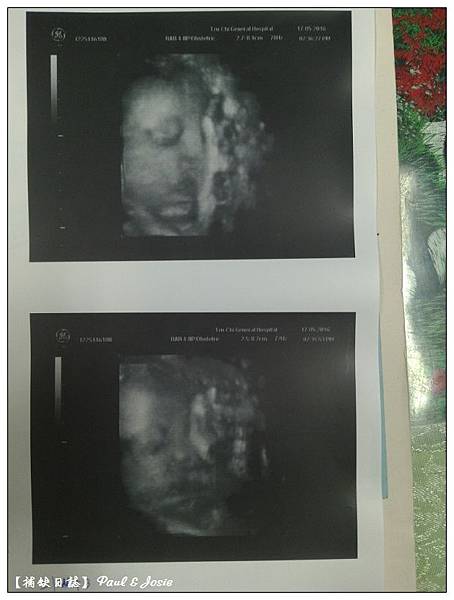

今天產檢有德妹半邊臉的3D照嘍!高醫生說妹妹長的有點像媽媽,

眼窩很深、鼻子好挺哦!醫生說其實也有點像哥哥阿得德。

那應該也是有點像爸爸耶....

因為德爸&德媽小時候的照片其實是滿像的,我們眼睛都很大!

(高醫生有說到,因為胎位不正,所以德妹的頭骨橫徑會偏小,

可是他看到德媽的肚子這麼大, 倒不覺得妹妹會太小哦)

2016/05/17第八次產檢 31w+3d 女寶寶頭骨橫徑7.6cm,1560g 。